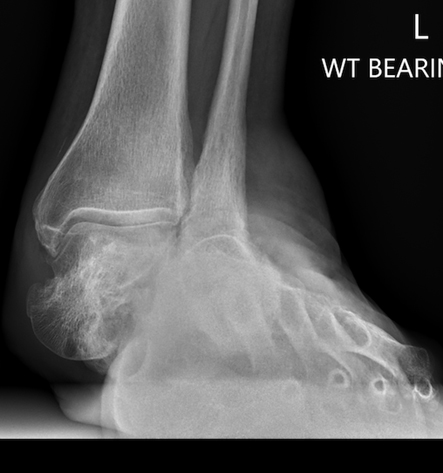

TOTAL ANKLE REPLACEMENT :: ORIF CALCANEUS :: ORIF ANKLE FRACTURE DISLOCATION :: COMPLEX BUNION AND LESSER TOE CORRECTION :: TALUS FRACTURE -1 :: TALUS FRACTURE -2 :: LISFRANC REPAIR :: COMPLEX TRIPLE ARTHRODESIS 1 :: COMPLEX TRIPLE ARTHRODESIS 2 :: MINIMALLY INVASIVE BUNION REPAIR 1 :: MINIMALLY INVASIVE BUNION REPAIR 2 :: ARTHROSCOPIC CARTILAGE REPAIR :: TENEX SPUR DEBRIDEMENT :: Haglunds Debridement and Achilles Repair